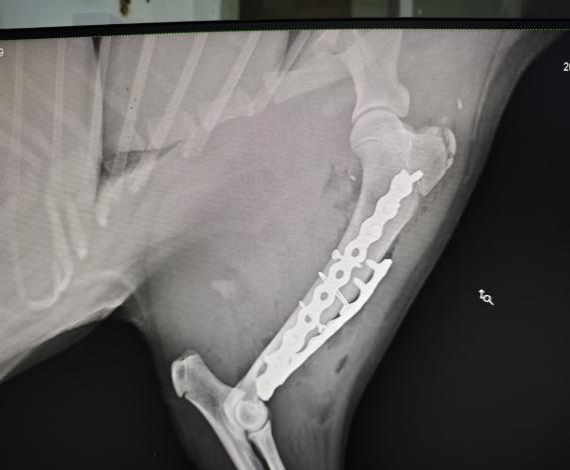

手术后左前肢侧位X光